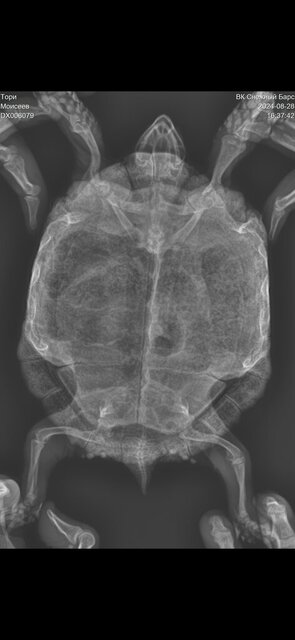

Сделали рентген, я не понимаю, но кажется что, что-то не так с легкими

Посмотрите пожалуйста

9). Рентген в дорсовентральной проекции с вытянутыми конечностями. Для исключения суставной подагры в виду отёков на суставах задних конечностей и патологий в костных структурах.